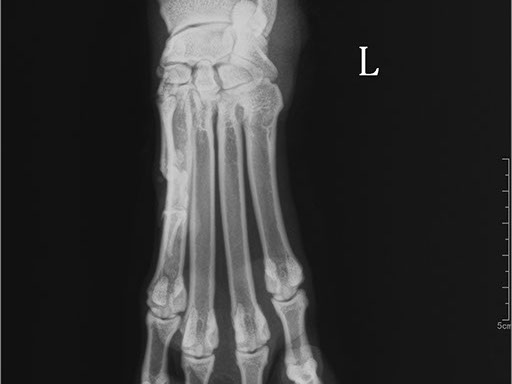

Цифровая рентгеновская установка ASR-6150C поставляется с мобильным столом пациента и комплектом рентгенопрозрачных анатомических ложементов всех размеров, видов и пород домашних животных.